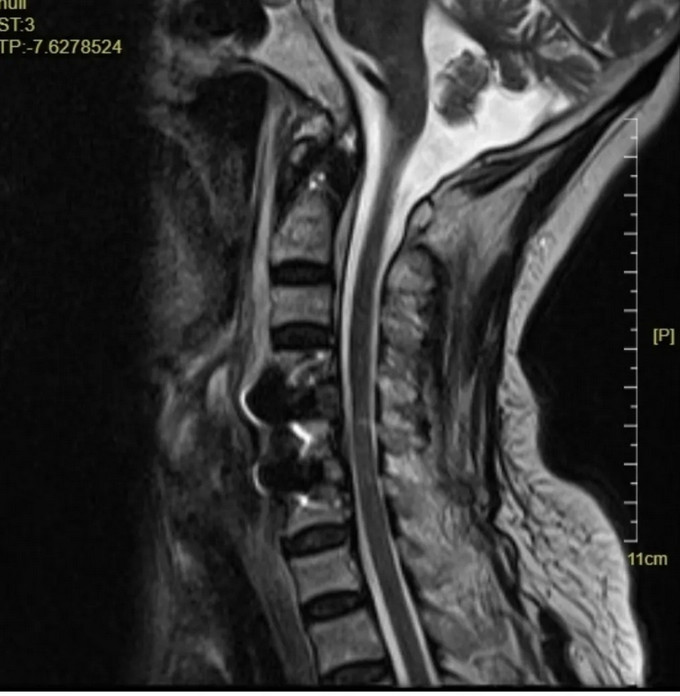

頸椎MRI橫斷位

頸椎MRI矢狀位,可以看到患者的頸神經(jīng)被明顯壓迫